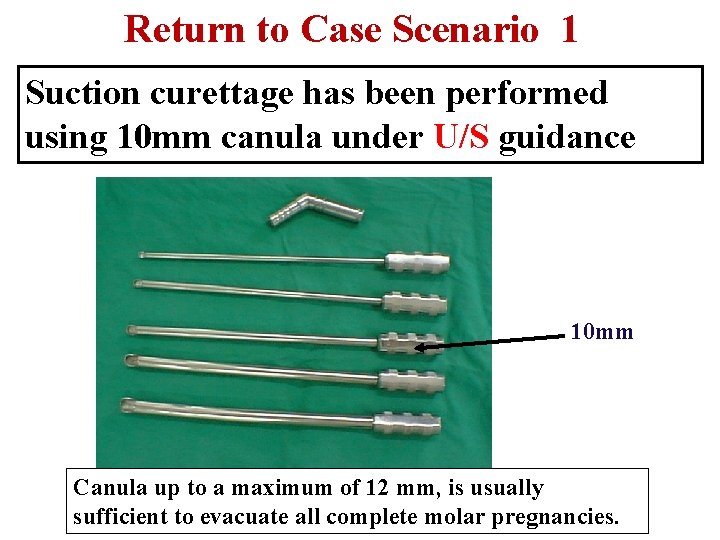

Return to Case Scenario 1 Suction curettage has been performed using 10 mm canula under U/S guidance 10 mm Canula up to a maximum of 12 mm, is usually sufficient to evacuate all complete molar pregnancies.

U/S Guided Suction Curettage Suction curettage can be performed under U/S guidance to: Facilitate the procedure Confirm complete evacuation of contents. Garner Up. To. Date 2010